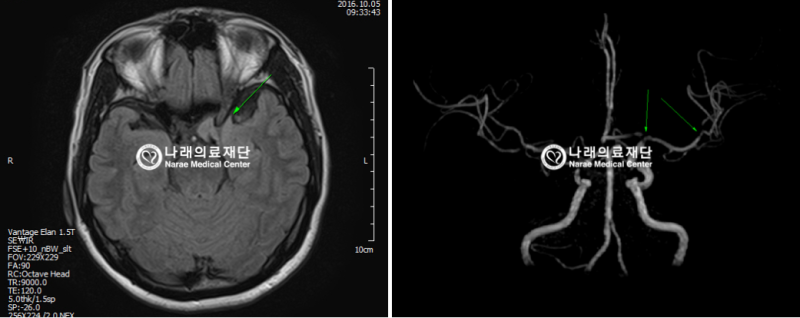

반면에 MRA(자기 공명 혈관 영상)는 MRI의 일종으로, 혈관의 이미지를 생성하는 데 초점을 맞추고 있습니다. 이는 혈관의 구조 및 흐름을 평가하는 데 유용하며, 주로 심혈관 질환의 진단에 사용됩니다. MRA는 특히 혈관의 협착이나 막힘, 동맥류와 같은 혈관 관련 문제를 발견하는 데 매우 유용합니다.

MRA는 MRI의 기법을 기반으로 하므로, 기본적으로는 동일한 작동 원리를 가지고 있지만, 약간의 차이점이 있습니다. MRA는 특히 혈관을 시각화하는 데 최적화되어 있으며, 주로 조영제를 사용하여 혈관을 더욱 뚜렷하게 구분합니다. 조영제는 혈관 내에서 신호의 차이를 만들어 신호 강도를 높여줍니다. 이로 인해 혈관의 형태와 상태를 더욱 명확하게 시각화할 수 있습니다.

- 혈관 질환의 조기 발견에 특화되어 있다.

- 비침습적인 방법으로 혈관 상태를 평가할 수 있다.

- 동맥류 및 혈관 협착의 평가

- 심혈관 질환 위험 환자의 혈관 상태 진단

- 선천적 심장 질환 및 혈관 기형의 확인